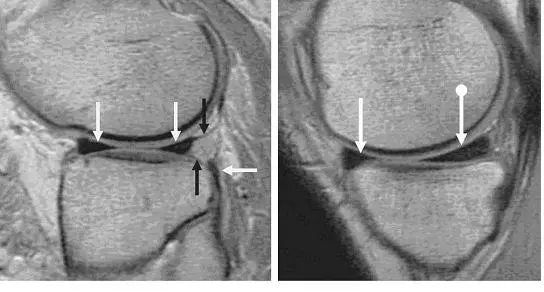

图 4 半月板横韧带

左图:横断面 T1 像显示半月板横韧带连接内侧半月板(白色圆箭头)和外侧半月板(白色直箭头)的前角;右图:经过半月板横韧带(黑色箭头)的矢状面,可见半月板横韧带与半月板前角之间的间隙呈现高信号(白色箭头),易误诊为半月板撕裂。